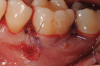

Fig 1. Tooth No. 19 at presentation, buccal view.

Figure 1

In the case presented, a 56-year-old healthy nonsmoking male patient, diagnosed with periodontitis stage III, localized, grade B, had been under care in a private practice periodontal office (RAL) for 25 years. He had a history of good compliance with his treatment (full-mouth plaque score <20%). During the COVID-19 pandemic, the patient missed three supportive periodontal therapy (SPT) visits over a year, resulting in periodontal breakdown interproximal between teeth Nos. 18 and 19 (mandibular left second and first molars, respectively). At his most recent periodontal maintenance visit, significantly increased periodontal probing depths of up to 10 mm with bleeding on probing were noted (Figure 1 through Figure 3). The periapical radiograph revealed a deep, narrow three-wall intrabony defect at the distal aspect of tooth No. 19, with class I buccal furcation involvement (Figure 4). According to the periodontal risk score (PRS),15 formerly known as the Miller-McEntire periodontal prognosis index, the tooth prognosis at the patient's initial examination was "good" (score = 5), taking into account that he was unaware of his hemoglobin A1C (HbA1c) levels. This scoring motivated the patient to be tested, and his follow-up HbA1c was <6%, thus reducing his PRS to 3, which was considered "excellent," as the PRS target goal for regenerative procedures is a score of <5.15